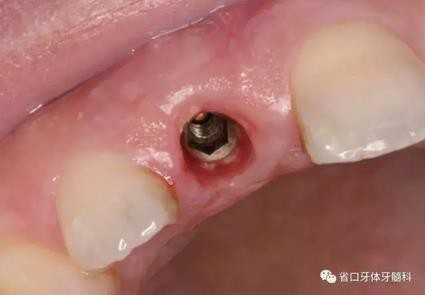

圖1 術(shù)前口內(nèi)照

圖2 術(shù)前口內(nèi)照

圖3 術(shù)前口內(nèi)照

(1)微創(chuàng)拔牙及即刻種植:術(shù)前拍攝口內(nèi)照及實(shí)施牙周基礎(chǔ)治療。常 規(guī)消毒鋪巾阿替卡因局麻下微創(chuàng)拔除上頜右側(cè)中切牙,搔刮拔牙窩及根尖肉 芽組織。探測(cè)牙槽骨唇側(cè)骨壁及鄰面牙槽嵴完整,牙齦無(wú)撕裂。不翻瓣下于上頜右側(cè)中切牙缺隙近遠(yuǎn)中中點(diǎn)的腭側(cè)牙槽骨及根方定位,按照逐級(jí)預(yù)備的原則,緊貼牙槽窩腭側(cè)骨壁制備種植窩洞,植入Zimer®3.7mm×13mm TSV種植體1顆,植入扭矩>35N·cm,以O(shè)sstell測(cè)量種植體的ISQ值為68。 種植體平臺(tái)位于唇側(cè)齦緣中點(diǎn)下3mm,與唇側(cè)骨壁內(nèi)側(cè)面形成的跳躍間 隙約2mm,置入Bio-Oss®細(xì)顆粒骨粉0.25g,上愈合基臺(tái)關(guān)閉創(chuàng)口。術(shù)后 CBCT檢查顯示:種植體利用牙槽窩根方骨質(zhì)固位,緊貼牙槽窩腭側(cè)骨壁, 其唇側(cè)面與牙槽窩唇側(cè)骨壁的內(nèi)側(cè)面所形成的跳躍間隙(約2mm)可見(jiàn)顆 粒狀顯影物充填。牙槽窩的唇側(cè)骨壁及唇側(cè)倒凹無(wú)缺損穿孔。